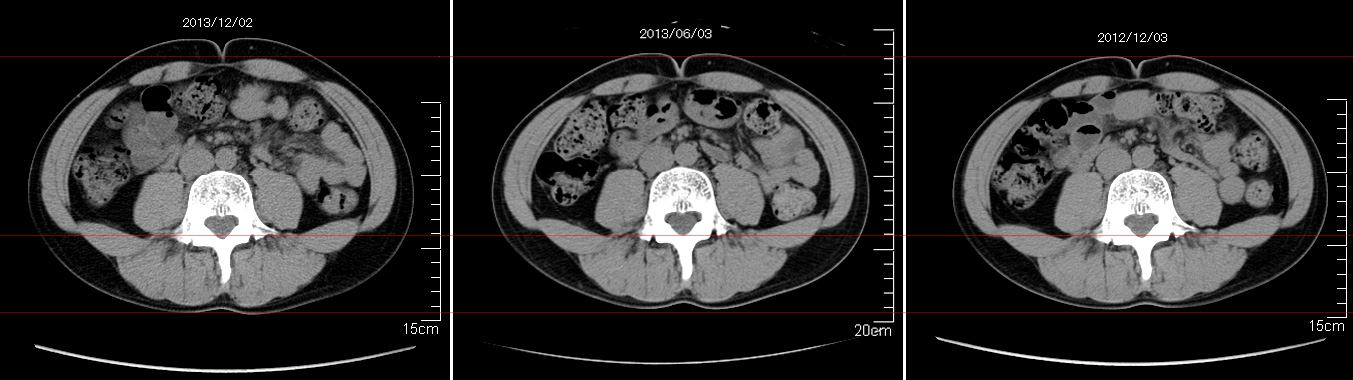

マーカー、CT画像、問題なし!!

左から2013年12月、2013年06月、2012年12月と背骨の位置は合わせて並べてみた。

6月まではあまり変化がなかったが、この半年で明らかに違う。

背中側の脂肪がやや増えてはいる。

でも最も大きな違いは、腸なのか、やたらと内臓が膨れている・・・。

一言で言うと食べすぎ?!?!

食事は野菜中心ではあるが、確かによく食べているw。

半年に一回の定期検査である。

6月より太ったからCT画像の腹脂肪が気になる・・・。